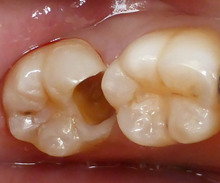

全部 虫歯をとりました。

こんなに 大きな穴が開いてしまいました。

レントゲンを使用した、定期健診 が大事ですね!!